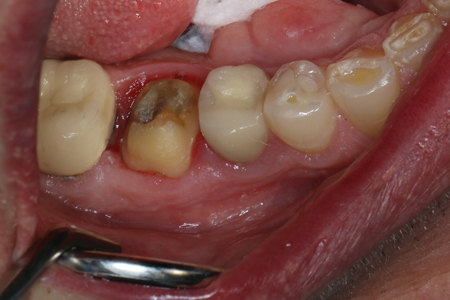

TheraCem exhibits minimal resistance to seating, but is not runny (figure 3). Cleanup is easy with hand instruments and floss (figure 4). For deeper subgingival margins, this cement is kind to the gingiva, although the margins should be thoroughly inspected to ensure complete removal of excess cement (figure 5).

Figure 4: TheraCem being cleaned up